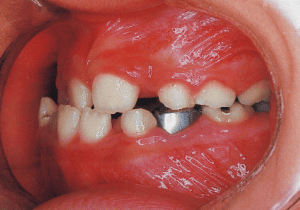

10 Perform lateral expansion of maxilla 7-4-’90 Midline is becoming deviated 9 years

11 During observation 4-1-’93 Midline deviation has become even greater 11 years 9 month

The Edgewise appliance was applied locally (8) and removed after 11 months (9). However, as the maxillary molar region gradually became crossbite, the maxillary arch was laterally expanded using a quad helix.

X-rays confirmed significant differences in the length and orientation of the mandibular ramus on the left and right sides. It was determined that orthodontic treatment alone would be insufficient, and a decision was made to proceed with treatment incorporating surgical intervention.